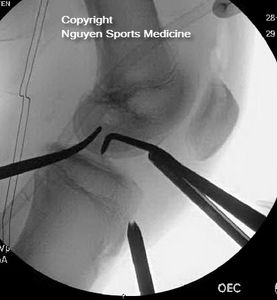

- Pediatric ACL Surgery